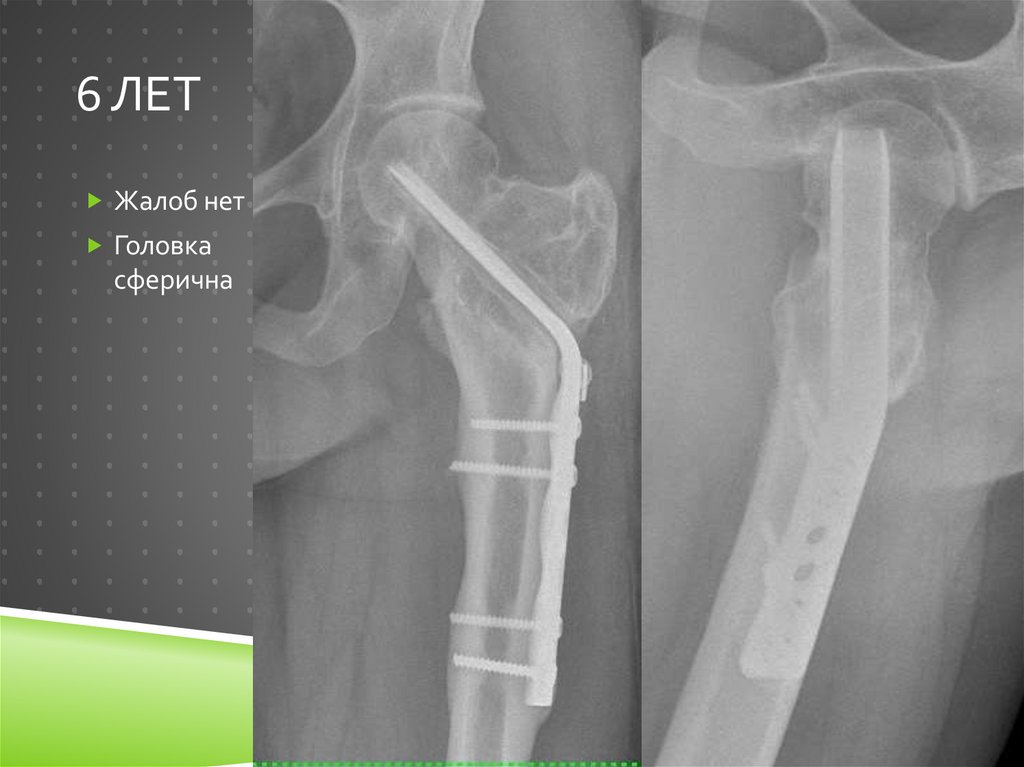

44. 6 лет

6 ЛЕТ

Жалоб нет

Головка

сферична